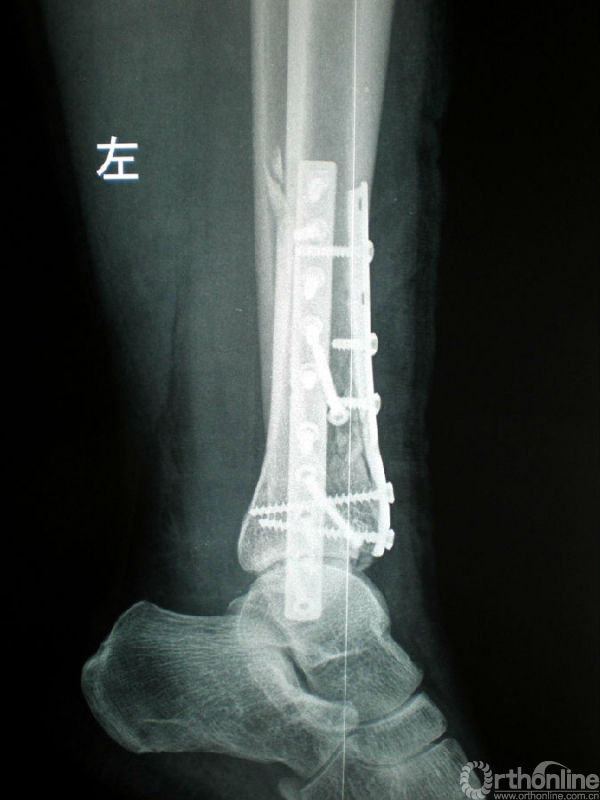

图4 男,41岁,左侧双柱pilon骨折。

4c.手术入路及1/3半管型钢板分柱固定情况;

4d.术后X线正侧位片示双柱pilon骨折对位、对线良好。